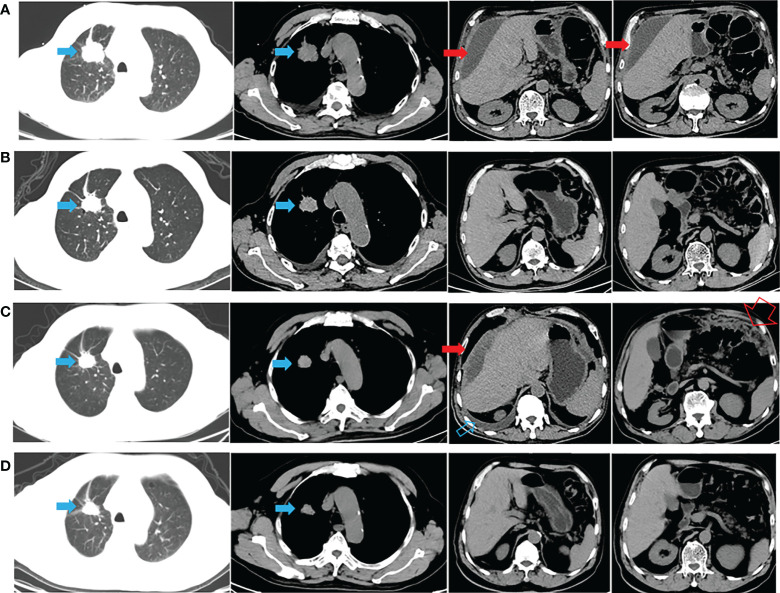

一名有大約 20 包年吸煙史的 72 歲男性主訴腹脹,于 2020 年 9 月 22 日入院。胸腹計(jì)算機(jī)斷層掃描 (CT)(圖 1A)和放射性核素骨掃描顯示 2.8 厘米的右上肺腫塊、胸水、腹水和多處骨轉(zhuǎn)移(顱骨、右鎖骨、多處椎骨和骨盆)。 彩色多普勒超聲診斷左頸淋巴結(jié)轉(zhuǎn)移。 CT引導(dǎo)活檢示腫塊為肺腺癌,診斷為右上肺腺癌多發(fā)轉(zhuǎn)移(cT1bN3M1c,IVB期)。 2020 年 10 月 8 日,通過(guò)對(duì)一組 8 個(gè)癌癥相關(guān)基因的下一代測(cè)序(NGS)分析了活檢組織。在 EGFR 外顯子 21(L858R)中檢測(cè)到突變(豐度:14.5 %) 和 PIK3CA 外顯子 8 (E474D)(豐度:36.6%),如圖 2A 所示。 患者接受了第三代 TKI almonertinib(110 mg/d)和雙膦酸鹽(唑來(lái)膦酸,4 mg,q4w)的一線治療。 賊初實(shí)現(xiàn)了疾病穩(wěn)定,但患者賊終經(jīng)歷了疾病進(jìn)展(出現(xiàn)胸水和腹水),無(wú)進(jìn)展生存 (PFS) 時(shí)間為 12 個(gè)月(圖 1B、C)。 疾病進(jìn)展后,患者入住當(dāng)?shù)蒯t(yī)院并接受順鉑(75 mg/m2,d1)和培美曲塞(500 mg/m2,d1)2個(gè)周期的化療。 然而,胸水和腹水沒有得到控制。 隨后,患者入院,腹水沉渣診斷為轉(zhuǎn)移性肺腺癌。 對(duì)腹水沉積物和 EGFR 外顯子 21(L858R)(豐度:1.7%)、EGFR 外顯子 18(L718Q)(豐度:0.8%)和 TP53 的突變進(jìn)行重復(fù)檢查 (V157F)(豐度:1.6%)被發(fā)現(xiàn)(圖 2B)。

圖1:整個(gè)治療過(guò)程中的 CT 表現(xiàn)。 (A) 診斷時(shí)的胸腹CT(胸腹引流后); (B) almonertinib 治療后 1 個(gè)月; (C)阿莫替尼耐藥后出現(xiàn)胸腹水(胸腹腔引流后); (D) 在阿法替尼加西妥昔單抗治療后 1 個(gè)月,胸水和腹水消失。 藍(lán)色實(shí)心箭頭表示原發(fā)病灶; 打開的藍(lán)色箭頭表示胸水; 紅色實(shí)心箭頭表示惡性腹水; 打開的紅色箭頭表示大網(wǎng)膜轉(zhuǎn)移。

與多學(xué)科團(tuán)隊(duì) (MDT) 討論了患者的病例。 重要的是,患者已充分了解擬議治療的益處和風(fēng)險(xiǎn),并簽署了知情同意書。 研究表明,與較高劑量的西妥昔單抗 (500 mg/m2) 相比,阿法替尼聯(lián)合較低劑量的西妥昔單抗 (250 mg/m2) 可能具有更高的耐受性。 因此,2021年11月16日開始阿法替尼(40 mg/d)和西妥昔單抗(250 mg/m2,q2w)聯(lián)合治療。1個(gè)月后CT顯示肺部和轉(zhuǎn)移灶穩(wěn)定,胸水和腹水控制良好( 圖 1D)。 然后,每 2-3 個(gè)月進(jìn)行一次隨訪,賊近一次隨訪時(shí)間為 2022 年 6 月 8 日。 輕微的胃腸道反應(yīng)是觀察到的少有不良事件 (AE)。 患者仍在接受聯(lián)合方案治療,生活質(zhì)量滿意,PFS近7個(gè)月。 從賊初的病理診斷開始,總生存期 (OS) 超過(guò) 21 個(gè)月(圖 1 )。